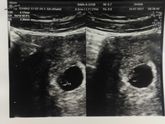

Не могу больше молчать)))) конечно для некоторых моих девочек это не новость, но думаю для большенства будет сюрприз))) Тадам… нам сегодня 11 недель и 5 дней!!!))) да да! Мы вновь ждем малыша!!!))) до этого срока было страшнее, а как вчера прошли скрининг, … Читать далее